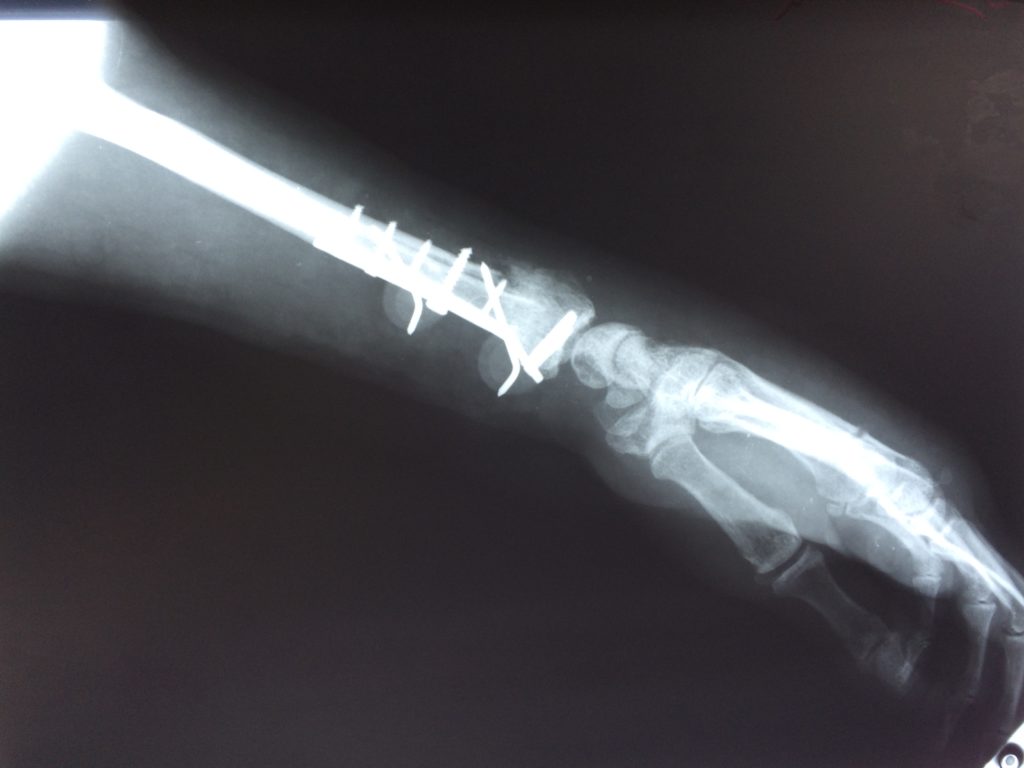

Операция - открытая репозиция, остеосинтез лучевой кости пластиной с костной ксенопластикой материалом "Остеоматрикс". На контрольных снимках в три месяца имеется консолидация перелома, миграции фиксатора нет, имеется остеоинтеграция ксенопластического материала.

Отдаленные результаты через 3 (три) месяца: